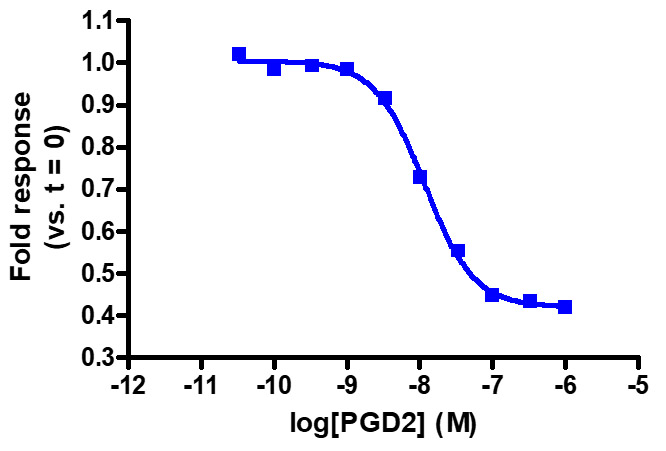

Sensitive enough to detect Gαi activity without forskolin. HEK293 cells expressing GPR44 were transiently transfected with pGloSensor™-22F cAMP Plasmid and treated with prostaglandin D2 (PGD2).